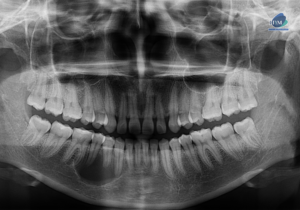

Paciente femenina de 38 años de edad acude al instituto de Diagnóstico maxilofacial – IDM (surco) para evaluación imagenológica general. En la radiografía panorámica (Figura

Paciente femenino de 11 años acude al Instituto de Diagnóstico Maxilofacial para realizarse un conjunto de estudios para ortodoncia. A la evaluación de la radiografía

Paciente femenina de 65 años acude al centro para una tomografía de cráneo completo para una evaluación general. A la evaluación de la radiografía panorámica

Paciente femenina de 56 años acude para evaluación de senos paranasales. A la evaluación de radiografía panorámica se observa aplanamiento del contorno condilar bilateral. La neumatización alveolar